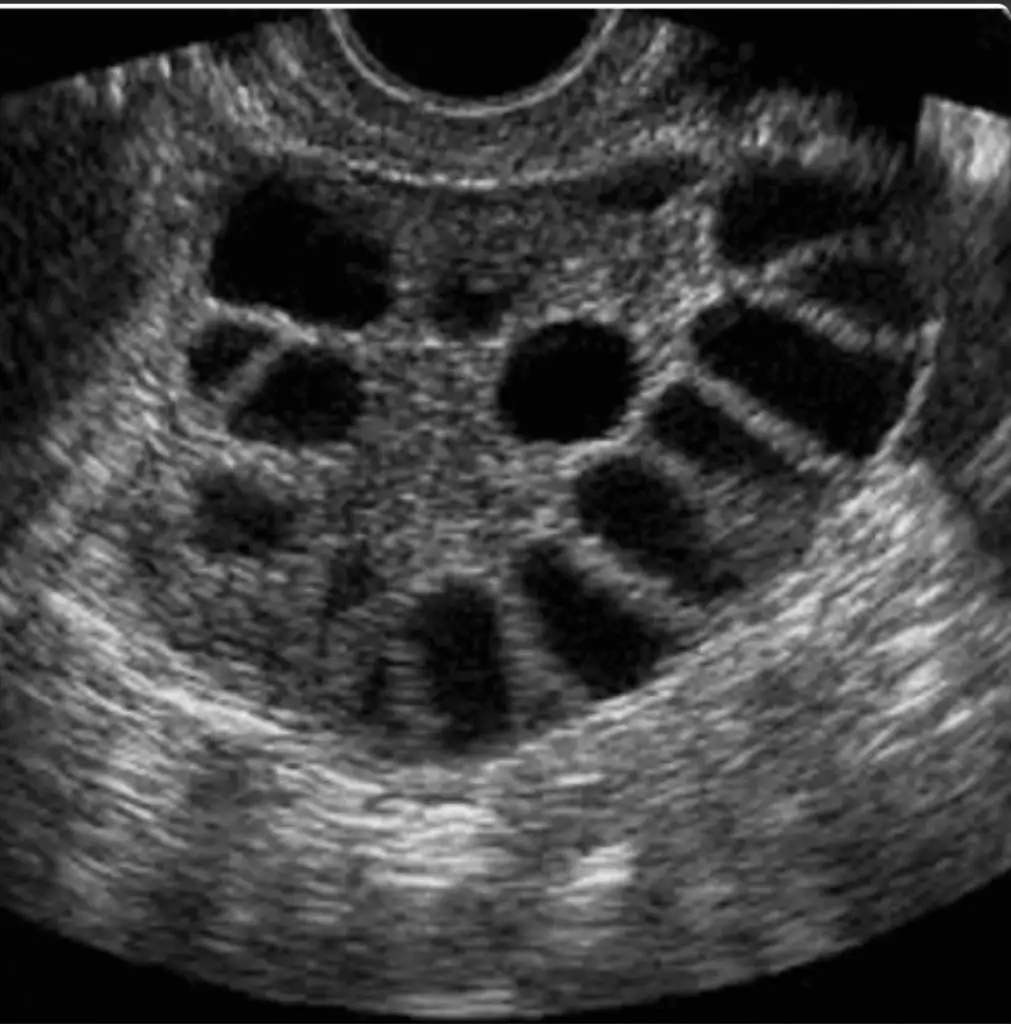

Kuzum yanlış mı biliyorum ama soğan kürü yumurtlama döneminden sonra yapılmaz diye biliyordum ben iyice araştırdın mı?Reglim bitince ertesi gün başladım kuzum küre beklenen adet 14 ocak 2 kere değerlendirmem oldu bugunude düşünüyorum hatta ilişkiden sonra çok pardon kıpkırmızı kan geldi o an kasıgımda karnımda ağrıdı muhtemelen çatladı bilmiyorum ama birşeyler oluyor hayırlısı![]()